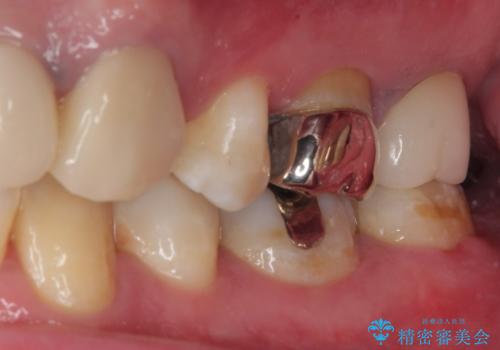

拡大鏡視野下で、保険のプラスチック、虫歯の除去を行い、セラミックインレーに適した形に整えました。

歯と歯茎の間に圧排糸と言われる糸を入れてシリコーン印象材にて精密な型どりをしました。

セラミックインレーの装着時には、唾液の侵入を防ぐために、ラバーダム防湿を行いました。